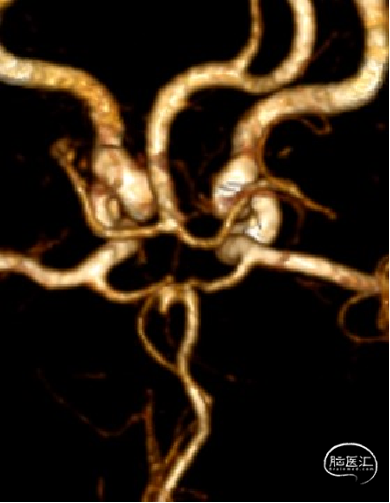

3D造影可见:前交通动脉可见约5.8mm*4.3mm动脉瘤,瘤颈宽3.5mm,三根大脑前。

3D造影可见:前交通动脉可见约5.8mm*4.3mm动脉瘤,瘤颈宽3.5mm。

前交通动脉可见约2.8mm*4.8mm大小动脉瘤,瘤颈宽3.1mm。

头颅CTA:右侧胚胎型大脑后动脉;前交通动脉瘤。

DSA示:前交通动脉可见约6.4mm*3.3mm大小动脉瘤,瘤颈宽2.0mm。